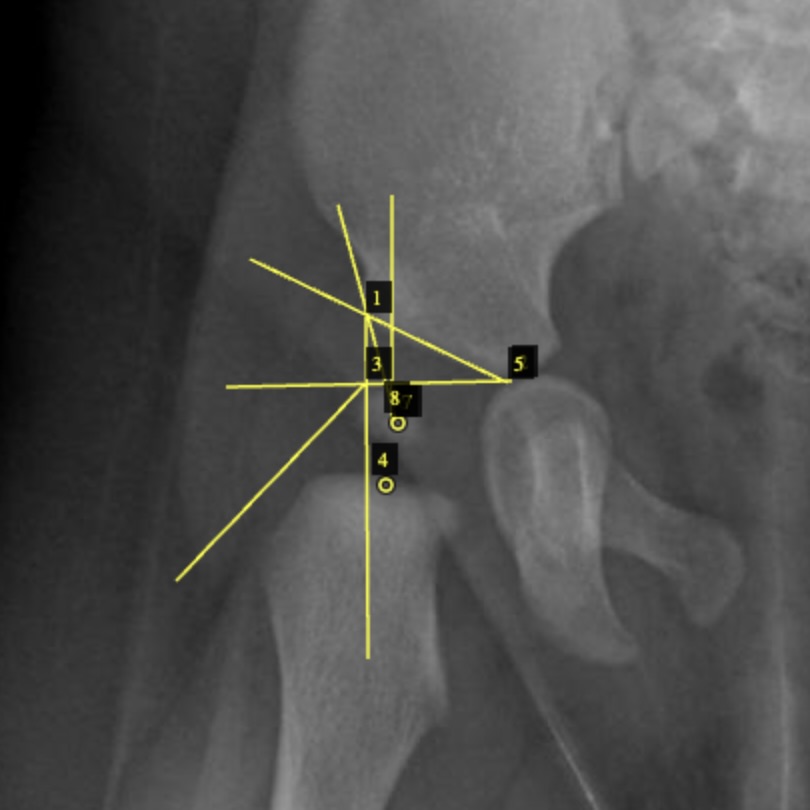

For each US image, the trainee recorded a horizontal baseline and lines, exposed/total femoral-head lengths, and an optional ossific-nucleus point. For each XR image, the trainee recorded Hilgenreiner’s H-line, Perkin’s P-line, a reference, the H-point, an acetabular index line, and CE-angle rays, with laterality handled explicitly. Numeric targets were derived by the standard acute-angle and ratio formulas (Graf ; coverage = exposed/total; AI = angle(H-line, AI-line); CE = angle(vertical, CE-ray); IHDI from the quadrant of the H-point).